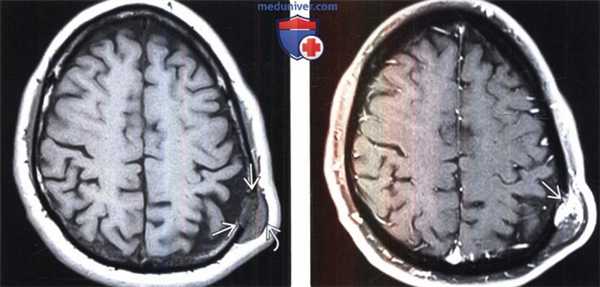

(Слева) КТ, костное окно, аксиальный срез: доброкачественные признаки гемангиомы в виде экспансивного образования с резко выраженными четкими фестончатыми контурами, «сотовой» или паутинообразной структурой на фоне интактных внутренней и наружной компактных пластинок.

(Справа) МРТ, Т2-ВИ, аксиальный срез: у этого же пациента визуализируются гиперинтенсивные компоненты образования, которые преимущественно обусловлены медленным кровотоком или венозным застоем в его сосудах в сочетании с наличием жировой ткани. Обратите внимание на «сотовые» или паутино-подобные гипоинтенсивные участки, соответствующие утолщенным трабекулам.